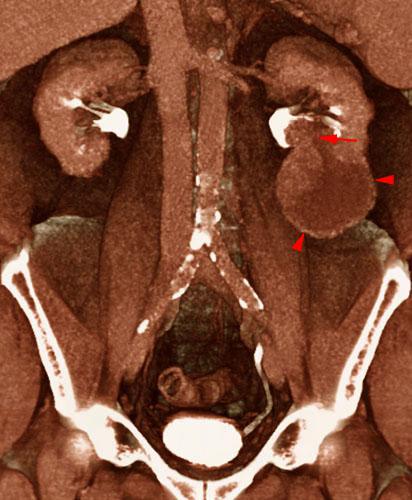

Tumor renal. Invasión de vía urinaria

VR seccional. Visión coronal anterior. TC contrastado en fase excretora. Tumor del polo renal inferior izquierdo con una zona necrótica (puntas de flecha) y una zona sólida que infiltra la pelvis renal (flecha)